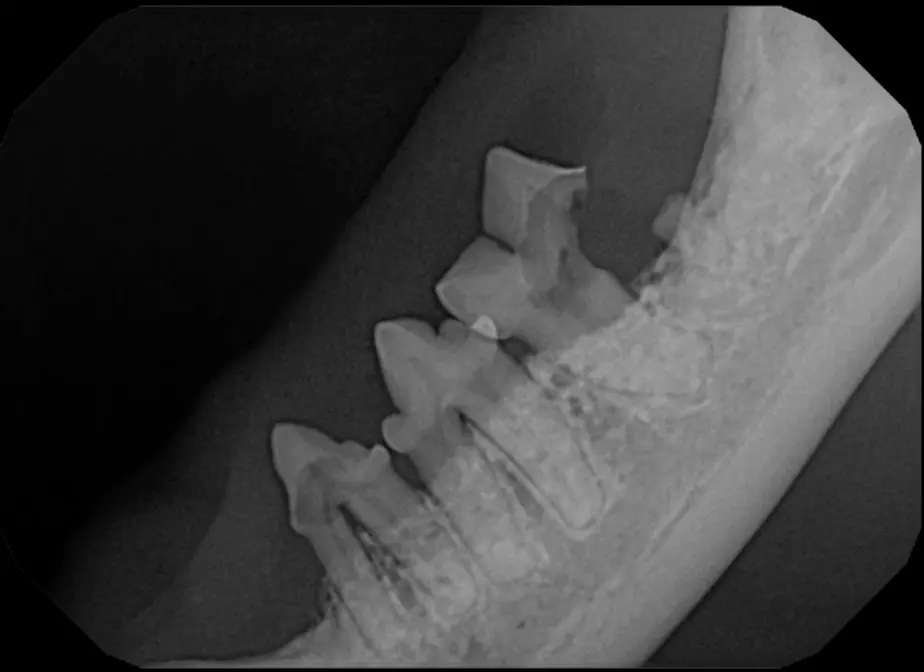

Root Canal Therapy

Root canal therapy is an excellent option for saving important teeth that have been fractured or are determined to be non-vital. The procedure is performed exactly as it would be for a human, except your pet will be dreaming peacefully under anesthesia. In many cases, root canal therapy is much easier on your pet than extraction, and preserves the structure of the tooth. It is important to have the root canal x-rayed periodically to monitor for any problems.

Vital Pulp Therapy

Young dogs less than 1 year of age that have very recently (less than 48 hours) fractured a tooth may be a candidate for vital pulp therapy. This procedure keeps the tooth alive and is very minimally invasive. For best results, this procedure should be performed within 48 hours of the tooth fracture. If your pet is not a candidate for this procedure, root canal therapy can still be performed to preserve the structure and function of the tooth. Vital pulp therapy can also be used to treat malocclusions.